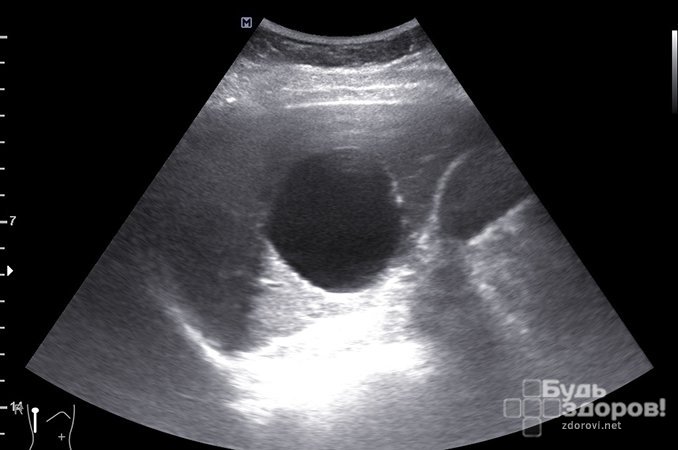

Чаще всего киста селезенки обнаруживается при проведении планового обследования, диспансерного осмотра или обследования по поводу заболеваний желудочно-кишечного тракта при выполнении компьютерной томографии или ультразвукового исследования.

Для установления диагноза используют те же методы, что и при других образованиях селезенки. Диагноз устанавливается на основании данных рентгеноконтрастного исследования сосудов селезенки — целиакографии. При наличии кисты селезенки определяется бессосудистая зона в проекции тени селезенки и смешение ее сосудов опухолью. При КТ выявляют четко очерченное образование низкой плотности.

Основным методом диагностики кисты селезенки является УЗИ. Кроме того, для выявления данного заболевания проводят такие процедуры, как МРТ, сканирование селезенки, анализы мочи и крови. Рост кисты можно контролировать благодаря плановым ультразвуковым исследованиям. Систематические обследования помогут врачу определить самый подходящий период оперативного лечения кисты селезенки.

- ультразвуковое исследование органа внутренней кисты селезенки. УЗИ является основным способом уточнения диагноза. Во время процедуры выявляют разновидность кисты, ее размер, место расположения на внутреннем органе;

- МСКТ селезенки – это сравнительно новый метод обследования. Процедура позволяет диагностировать размещение утолщения, размер и особенности более точно, чем прочие способы.